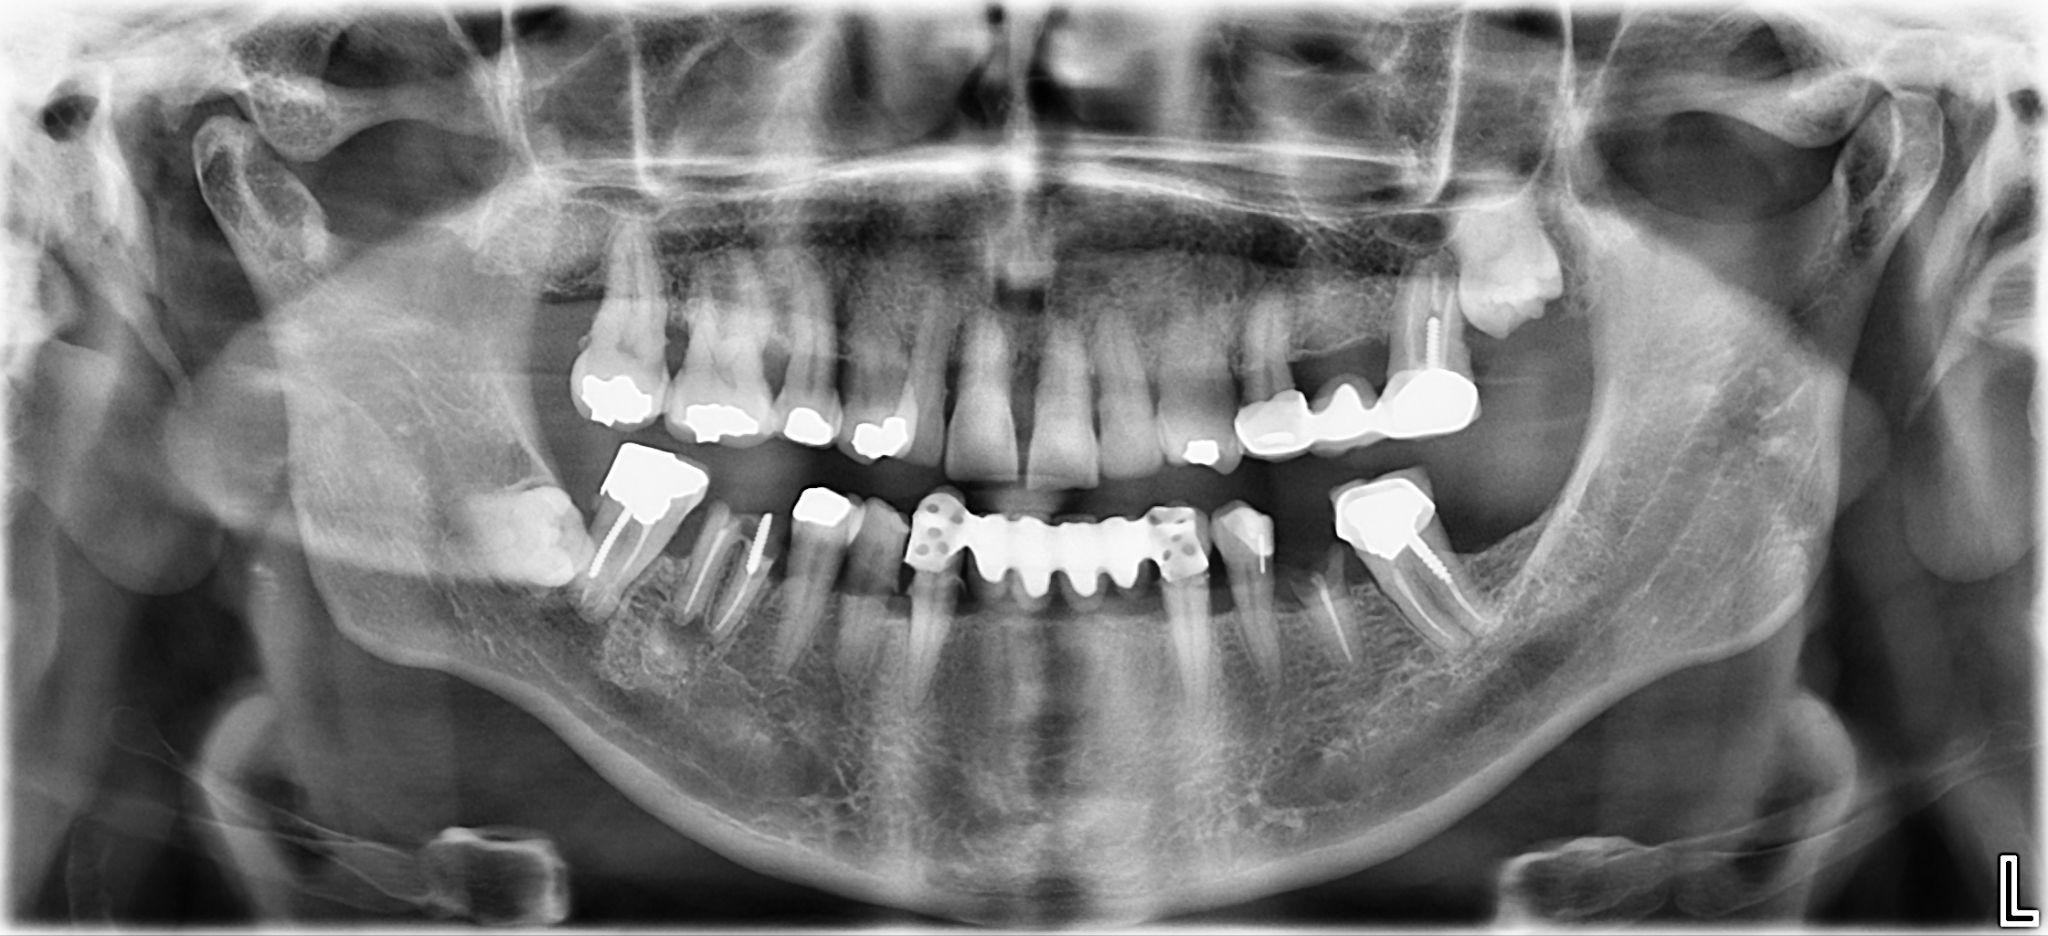

1. What option cannot be selected for the first quadrant of this panoramic X ray?

2 / 25

2. What option cannot be selected for the second quadrant of this panoramic X ray?

3 / 25

3. What option can be selected for the third quadrant of this panoramic X ray?

4 / 25

4. What option cannot be selected for the forth quadrant of this panoramic X ray?